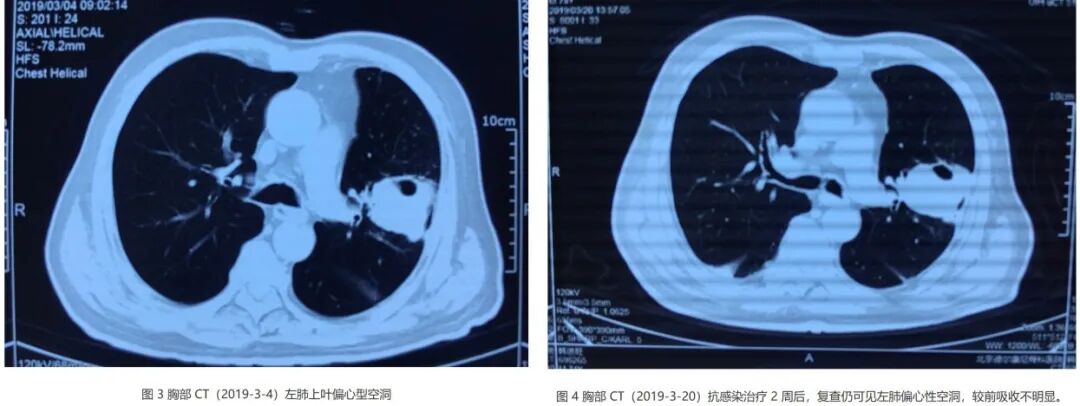

腰椎MRI检查提示「腰1-3水平椎管内及腰骶部,双侧腰大肌、竖脊肌内多发异常强化」,胸部CT提示左上肺类圆形厚壁空洞影,偏心性空洞。

复查胸部CT(图4)左肺空洞较前无明显变化。

病人第一次做胸部CT(左图,2019-3-4),明显看到左上肺类圆形厚壁空洞影,偏心性空洞。痰培养肺炎链球菌,但美罗培南治疗效果不佳。

抗感染治疗2周后复查胸部CT(右图,2019-3-20),较前吸收不明显,似乎还有一些增长的情况,提示给我们什么呢?查不到病原学导致不好治疗,为什么在明确病原学的情况下,治疗后影像学几乎没有变化呢?其实这个时候告诉大家,这样的病例应该积极明确穿刺,去寻找其他的病因。

入院后安排穿刺后提示肺鳞癌,伴坏死。免疫组化 CK7(-),Ki67(约 50% 阳性)。经过化疗和局部放疗后,病人得到改善。